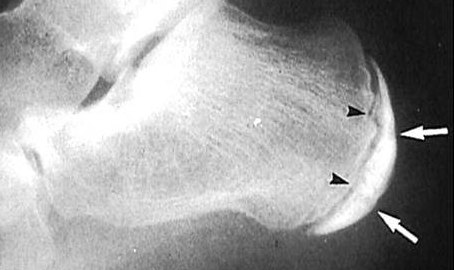

В качестве диагностических мероприятий могут быть применены рентгенография, КТ или МРТ стопы.